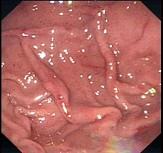

问题 女,49岁,上腹胀满5年,2个月来食欲不振,全身无力,胃镜如图,活检找到Hp,治疗用药为 ( )

选项 A.西米替丁 B.阿莫西林 C.氢氧化铝 D.胶体次枸橼酸铋 E.克拉霉素

答案 BDE